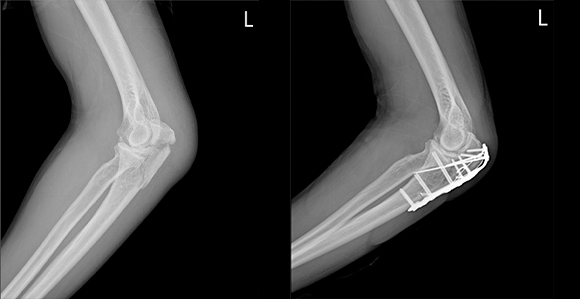

관혈적 정복이란 골절된 부위를 절개하고 뼈를 노출시켜 눈으로 직접 보면서 골절편을 정확하게 맞추는 방법으로 금속판과 나사 고정법, 핀고정법, 나사고정법, 골수 내정 고정법, 인공 관절 치환술, 외고정 기구 고정법 등등 여러 방식이 있습니다.

부위별 골절치료